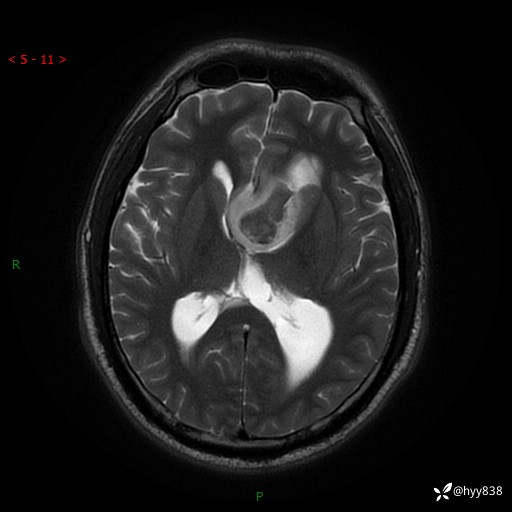

颅脑MRI平扫+增强